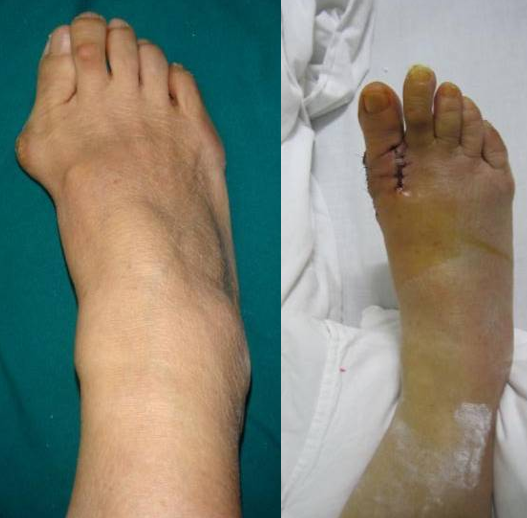

典型病例例1:姚X,女,78Y。

Chevron+第二跖骨Weil

例4:罗XX,女,60Y。

左足:第1-5跖趾关节脱位,足拇外翻。

胼胝体:第一跖骨内侧,第2/3跖骨头跖侧,第5跖骨头跖/外侧。

左足:第2-5趾爪形趾。

术式:左足:第1跖趾关节融合+第2-5跖趾关节成形术;右足:第4趾间关节融合+第5跖趾关节成形术